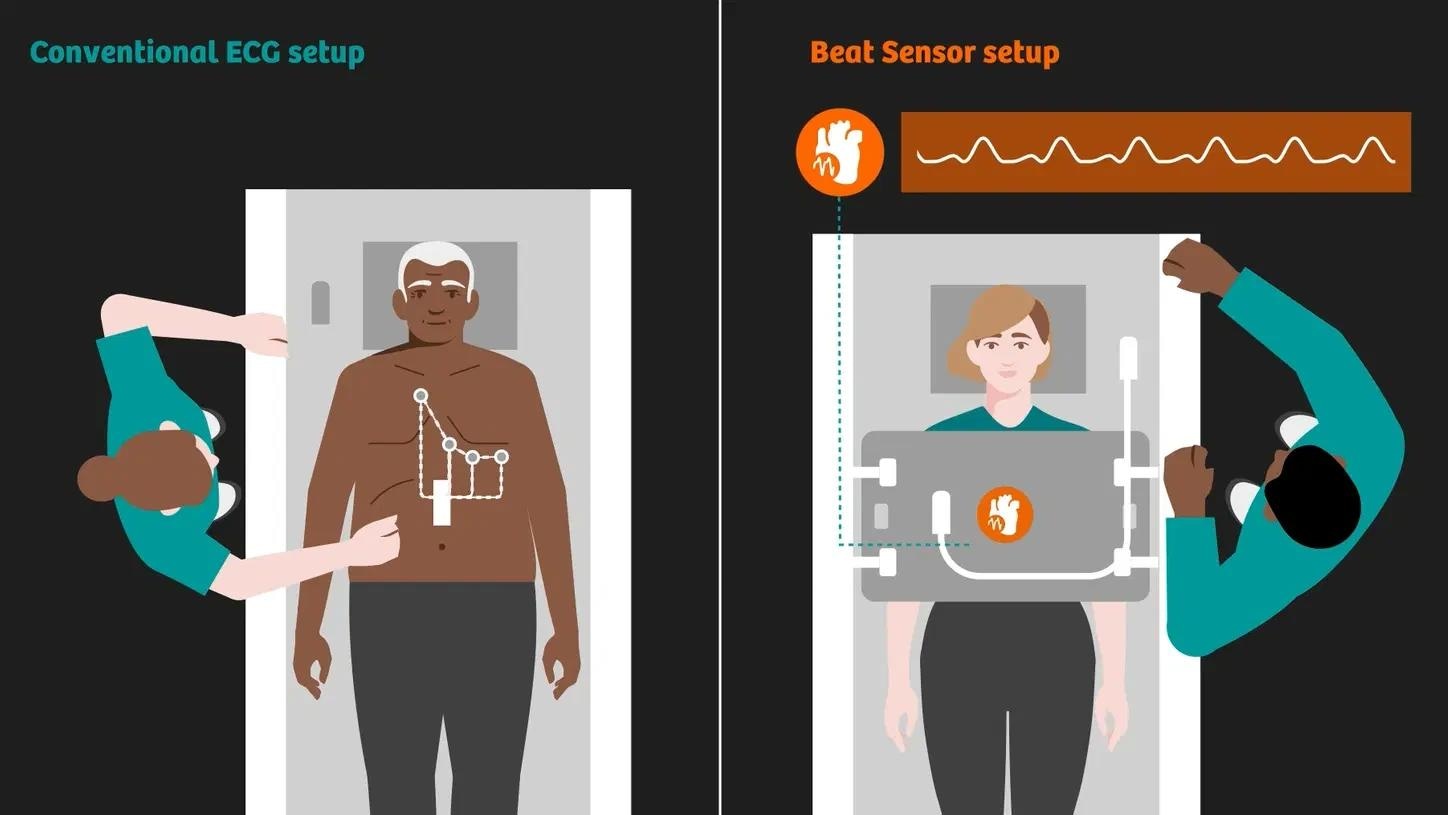

BioMatrix Beat Sensor

Complete cardiac MRI exams without the need for ECG leads. It improves patient comfort while speeding up the workflow.